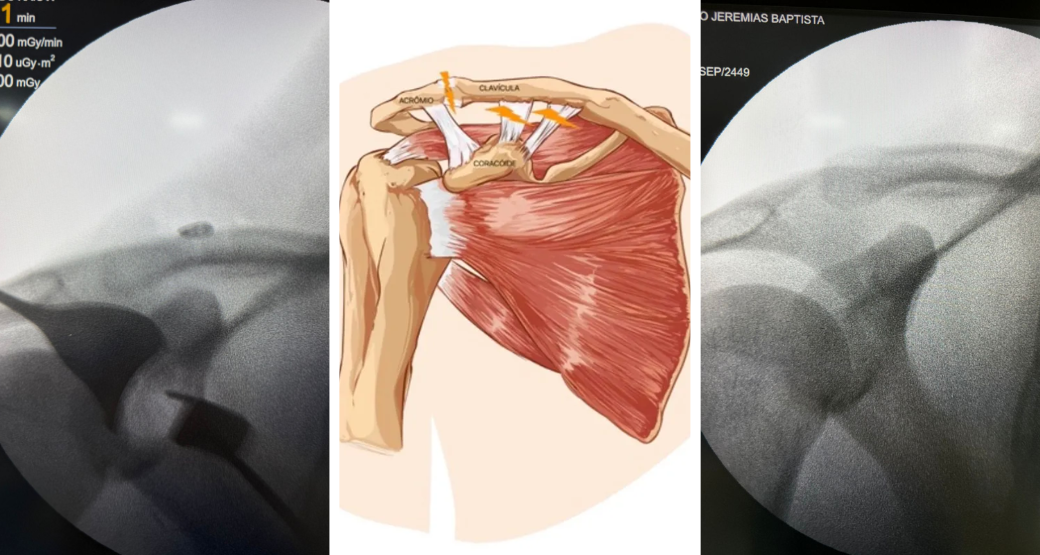

A Técnica TightRope foi a escolhida pelo cirurgião para realizar o procedimento.

A Thai Hope, como também é chamada, consiste em um sistema de fixação, com botões metálicos e uma sutura para estabilizar a articulação Acromioclavicular (AC).

“Utilizei dois pequenos botões conectados por um fio resistente. Um botão ficou abaixo do processo coracóide e o outro por cima da clavícula”, explica o cirurgião.

Ao ajustar a tensão desse sistema, Bastos rebaixou e estabilizou a clavícula, trazendo-a de volta ao seu lugar e mantendo a articulação firme.

Mostrou redução completa da luxação, o que aumenta muito as chances de recuperação satisfatória.